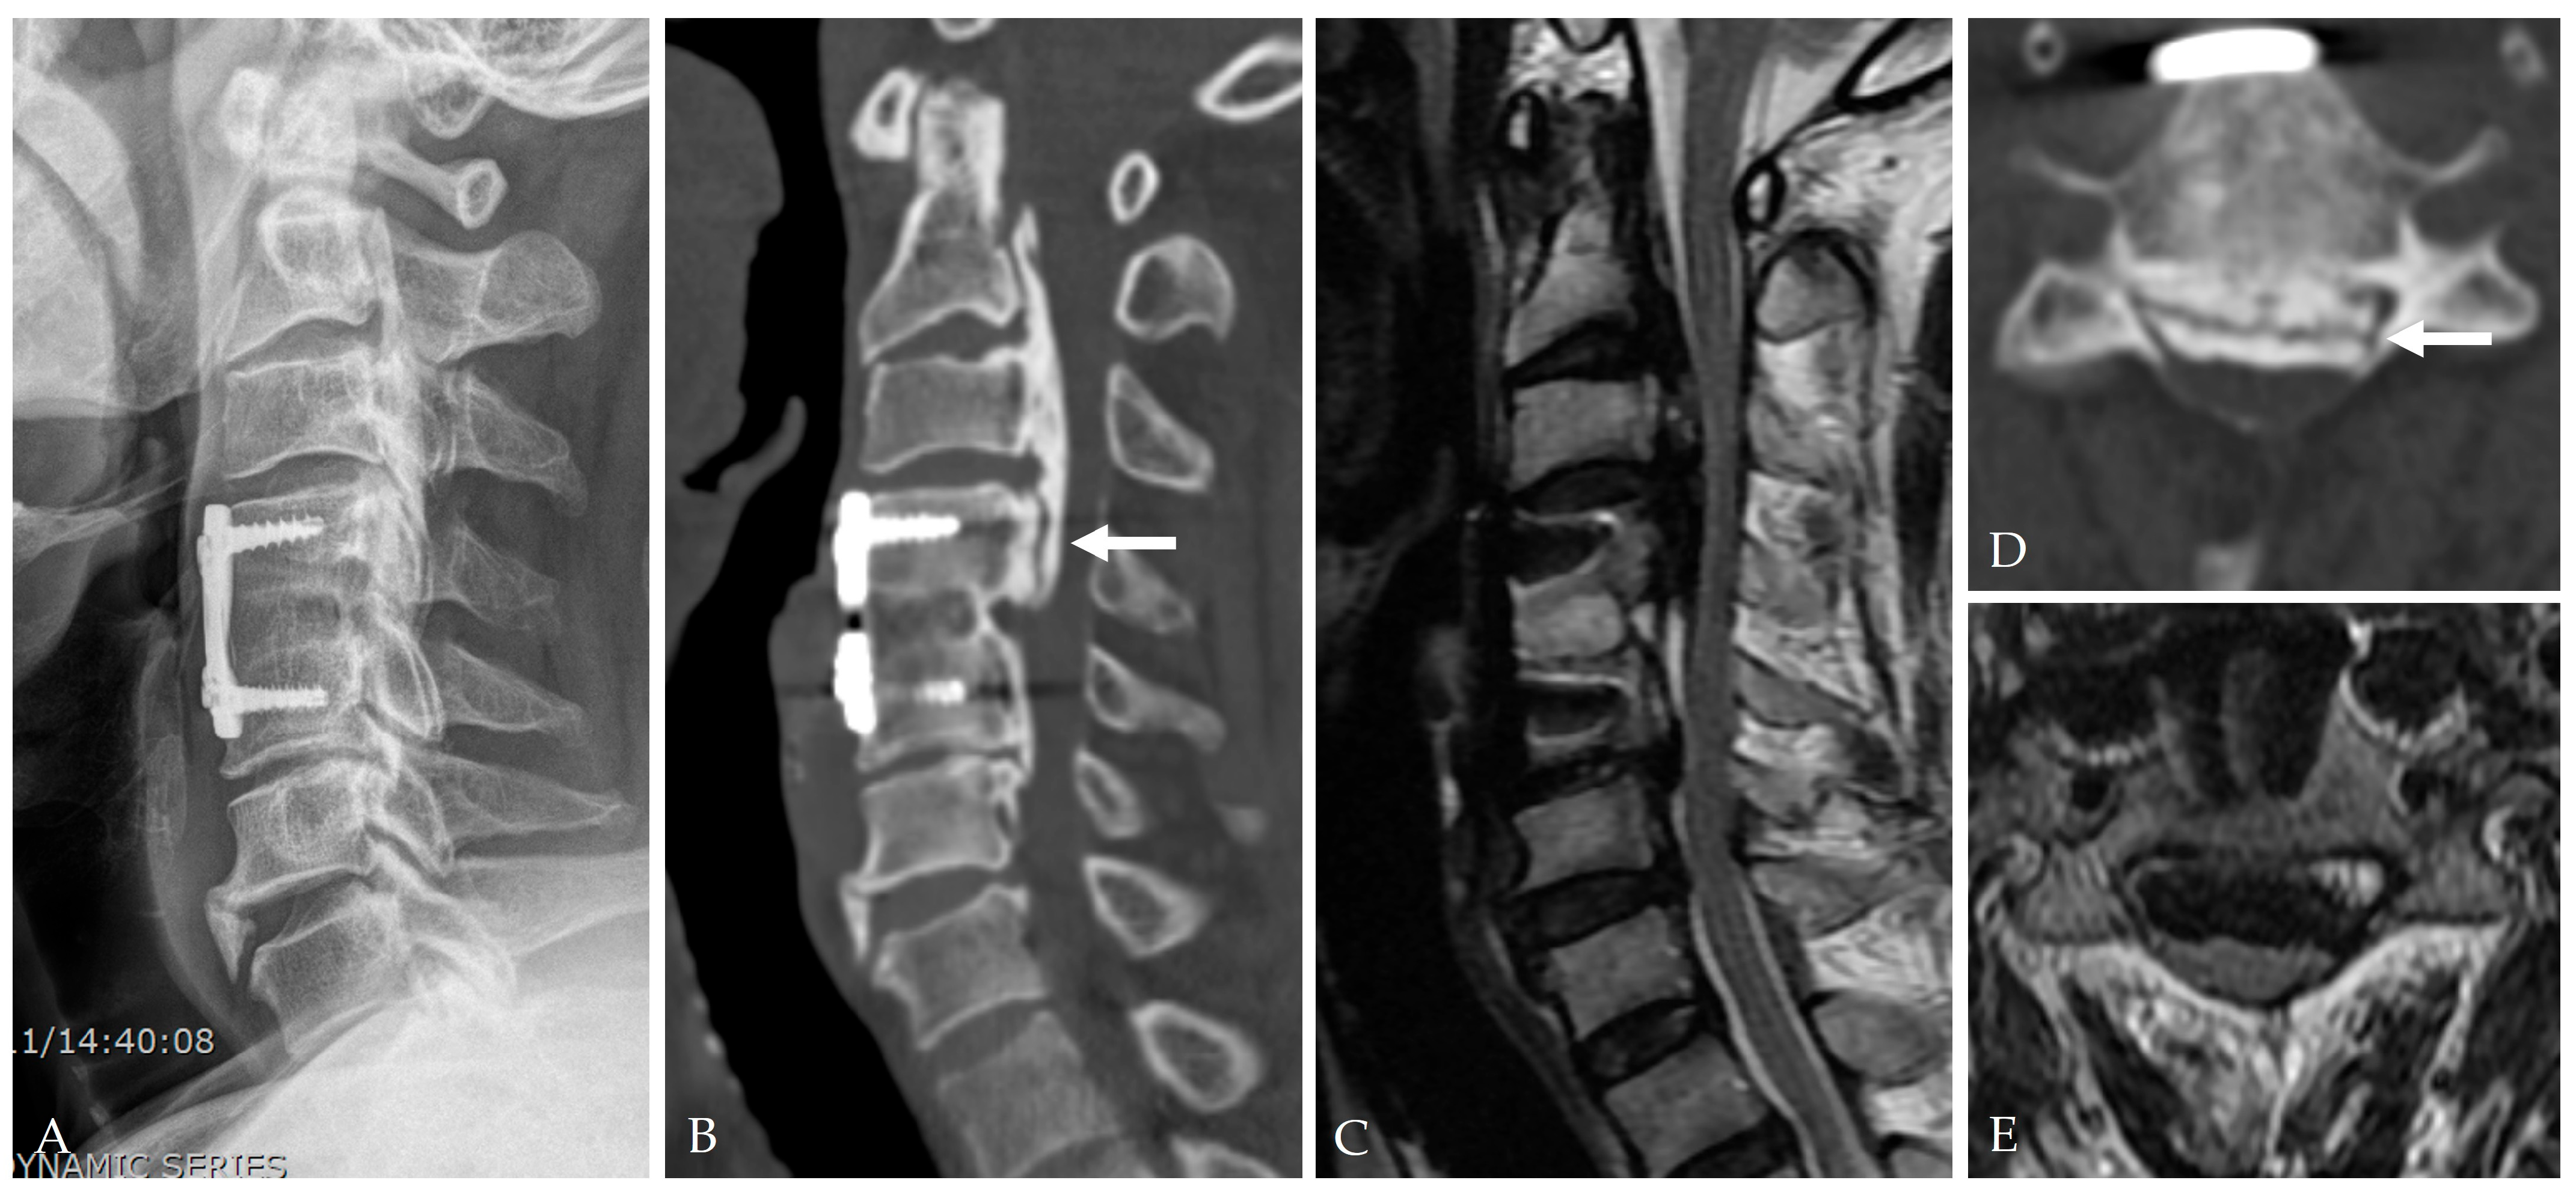

2.3. Patient-Related Risk Factors

6.3. Intracranial Hypotension and Remote Cerebral Hemorrhage

6.4. Mechanical/Implant-Related Complications

6.5. Pseudomeningocele and Late Recurrence